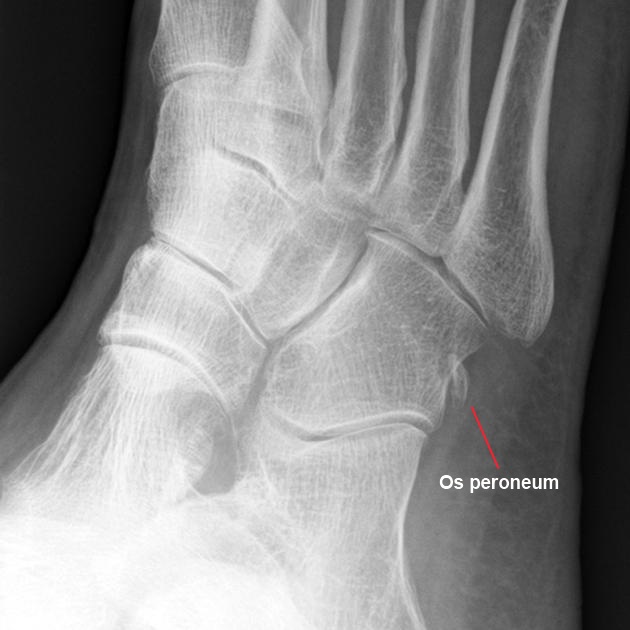

La radiografía es el estudio de primera línea para la exclusión de fracturas del maléolo lateral o el calcáneo, artrosis o cuerpos libres. También es útil para observar migración del os peroneum en ruptura del tendón del peroneo largo.

Os peroneum desplazado en ruptura tendón peroneo largo

Más importante aún, las radiografías permiten identificar una fractura del borde, que es una avulsión del retináculo peroneo superior del maléolo lateral. Una proyección en estrés del astrágalo también es útil: si hay más de 15° de inclinación, puede haber inestabilidad astragalina que conlleva a inestabilidad de los peroneos.